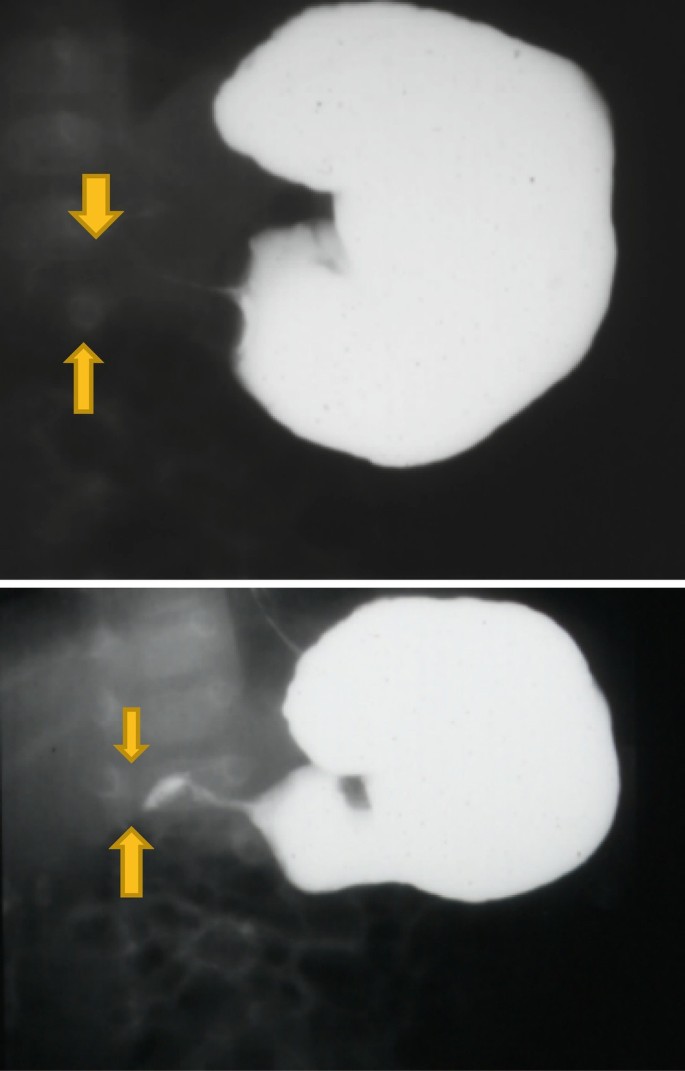

DBMCI Egurukul - ❓Upper GI series demonstrating a narrow and elongated pylorus with a narrow lumen (“string sign”), appearing as puckering of the mucosa (“double track sign”) is a feature of❓ A. The Gastrointestinal String Sign | Radiology Hypertrophic pyloric stenosis- “string sign” | Pediatric surgery, Pediatrics, Radiology Peds in a Pod on X: "If you've listened to Poopcast 3.0, check out this image of the “String sign” for pyloric stenosis. This is a the finding from an UGI, which Hypertrophic pyloric stenosis. ( ) A diagrammatic representation of the... | Download Scientific Diagram Pyloric Stenosis String Sign